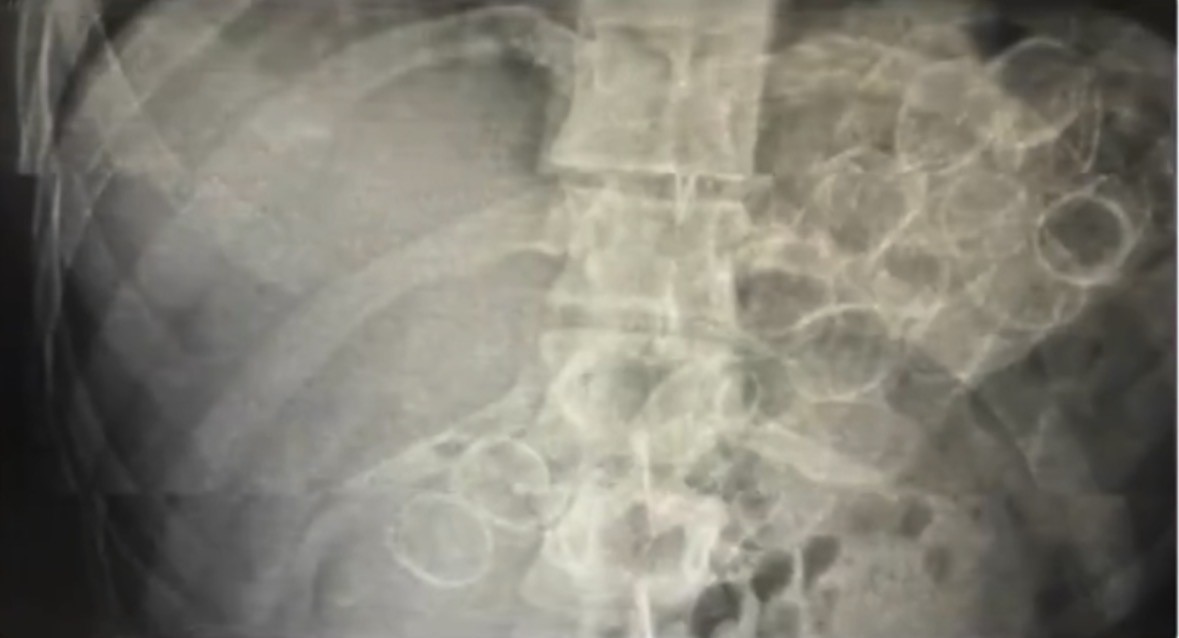

Bingöl’de polis ekiplerinin yaptığı çalışmada mide ve bağırsaklarında 75 kapsül halinde 775 gram metamfetamin maddesi ele geçirilen 3 şüpheli tutuklandı.

Bingöl İl Emniyet Müdürlüğü Narkotik Suçlarla Mücadele Şube Müdürlüğü ekiplerince yürütülen çalışmalar neticesinde, "Uyuşturucu veya Uyarıcı Madde Ticareti" suçu kapsamında 3 şahsın "yutma ve tıkma" yöntemiyle mide ve bağırsaklarında yüklü miktarda uyuşturucu madde taşıyarak kente getirdiği belirlendi. Ekipler tarafından yakalanan şüphelilerin hastanede yapılan tedavileri sonucunda, toplam 75 kapsül halinde 775 gram metamfetamin maddesi ele geçirildi.